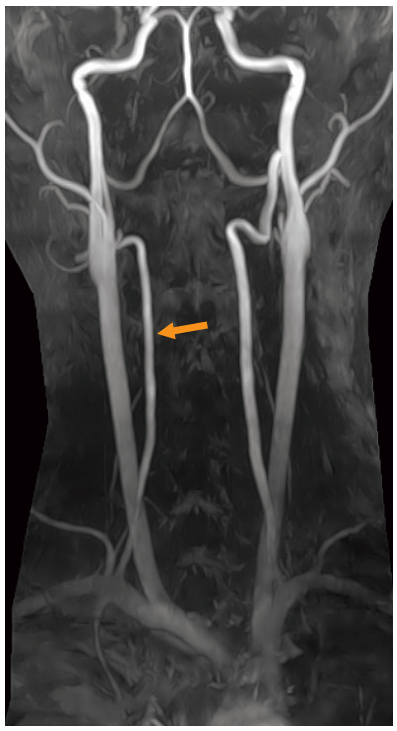

頸部MRA像を示す。

矢印で示すのはどれか。

- 外頸動脈

- 総頸動脈

- 椎骨動脈

- 内頸動脈

- 脳底動脈

答え 3